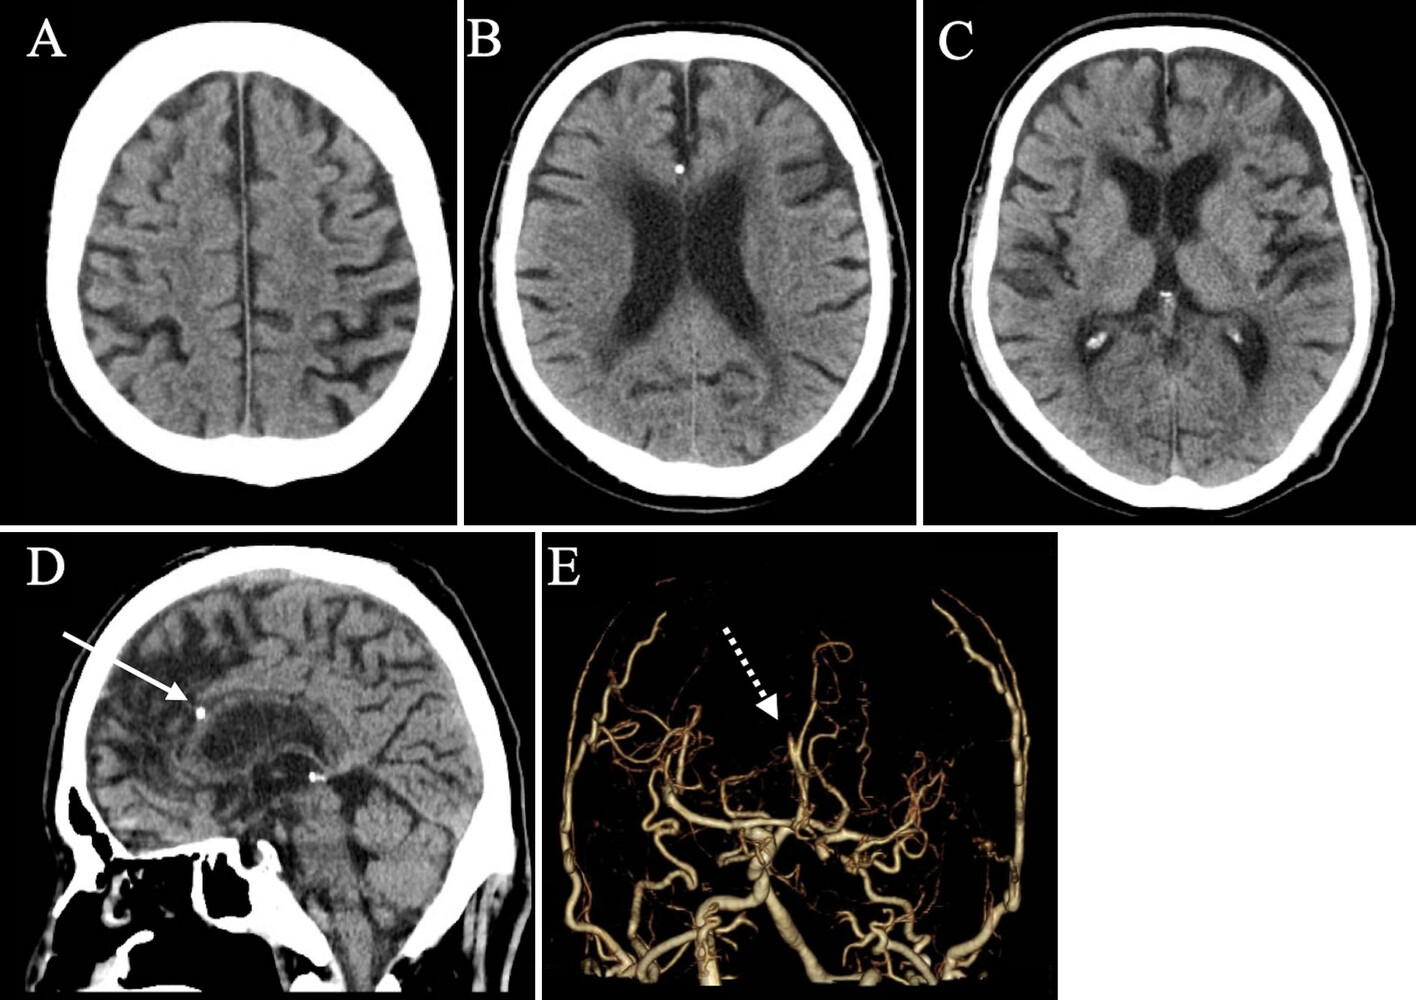

As featured in JNS Case Lessons, an 84-year-old man presented with sudden-onset left lower limb paralysis. Imaging revealed a right anterior cerebral artery (A3) occlusion caused by a severely calcified plaque. Despite IV alteplase and attempted mechanical thrombectomy, revascularization could not be achieved endovascularly.

Faced with deteriorating symptoms and a persistent occlusion, the neurosurgical team opted for an emergency endarterectomy via a bicoronal craniotomy and interhemispheric approach. The calcified lesion was surgically removed through a longitudinal arteriotomy. Intraoperative indocyanine green (ICG) angiography confirmed successful flow restoration.

The patient experienced near-complete recovery of motor function within 24 hours post-op and returned to walking independently. Histology confirmed the presence of calcified plaque with no evidence of active thrombus.

Microsurgical endarterectomy is a viable salvage option when EVT fails, especially for distal ACA occlusions with calcified lesions.

This case is the first documented instance of successful emergency endarterectomy for an A3 occlusion, achieving complete recanalization and favorable outcomes.

Preoperative recognition of calcification on CT should guide early consideration of open surgery.

Interhemispheric access was preferred due to less tissue disruption and better exposure in elderly patients with brain atrophy.

Longitudinal arteriotomy allowed thorough lesion visualization and safe removal.

⚠️ Intracranial arteries are fragile—careful technique is essential to avoid iatrogenic injury.